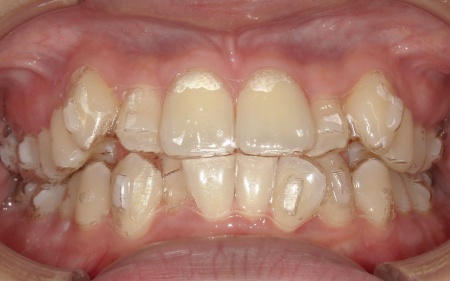

20代女性 八重歯と歯並びの乱れをマウスピース矯正装置で改善した症例

「上下の八重歯が気になる」とご相談いただきました。

拝見したところ、歯が正しく並ぶためのスペースが不足しており、歯が重なって生えてしまう叢生(そうせい)の状態が全体的に見られました。

特に上下の糸切り歯が外側にずれている、いわゆる八重歯が目立っています。

歯並びの乱れをこのまま放置すると、見た目が気になるだけでなく歯磨きが行き届きにくくなり、虫歯や歯周病のリスクが高まる可能性があります。

患者様の場合は上下あごの位置関係から噛み合わせに大きな問題はなく、横顔のバランスや鼻先とあごを結んだEラインにも目立った乱れは見られませんでした。

そのため、歯の位置や傾きを整えることで歯並びを改善できると診断しました。